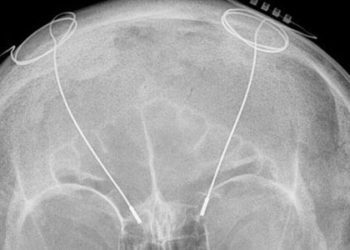

Image: PD 1. According to a pilot phase 1 trial, subcallosal cingulate Deep Brain Stimulation (DBS) appears to be generally ...